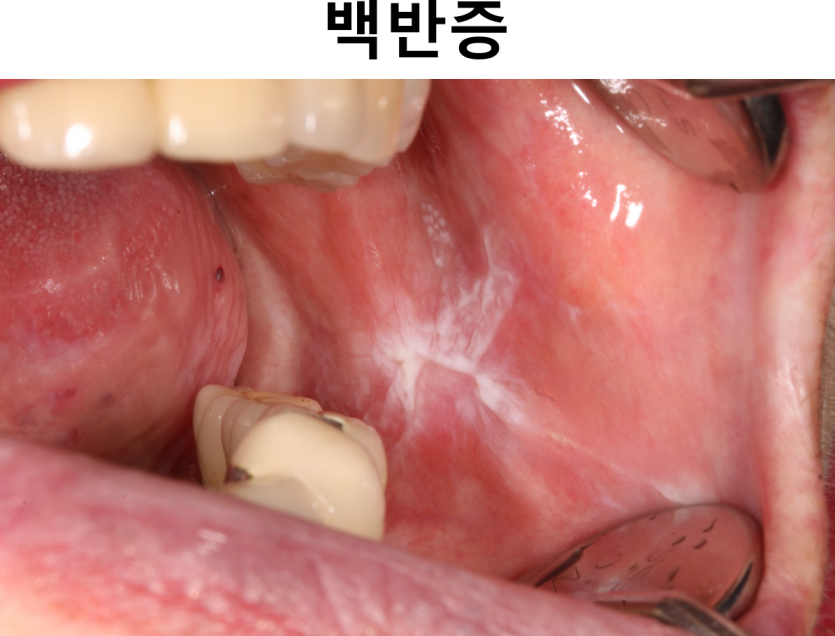

수포성궤양성 질환에서 노인들의 구강에 흔하게 발생 하는 질환은 편평태선, 다형홍반, 점막유천포창입니다. 편평태선은 노인들에게서 나타나는 수포성 궤양성 질환 중 가장 흔한 질환입니다. 편평태선은 피부, 점막 또는 양측에 다발성으로 나타나는 재발성의 만성 염증성 질환으로 표층부 상피와 결체 조직 사이의 접촉면에서 면역매개변성에 의해 야기되는 T 세포 매개 자가면역질환으로 알려져 있습니다. 편평태선은 주로 중년층에 호발하고 성별 간의 차이는 없으며 증상의 악화와 악화가 번갈아 일어나고 장기간 지속되는 것이 특징입니다. 구강 내 병소는 기본적으로 망상형, 구진형, 위축형, 미란형 및 수포형으로 구분될 수 있습니다. 위 사진의 망상형은 Wickham 선조라고 하는 레이스 모양의 백색선을 나타냅니다. 변연부의 경계는 명확할 수도 있지만 점차 희미해져 정상 소견으로 보이기도 합니다. 병소는 무증상이며 벗겨지지 않습니다. 구진형 편평태선은 소상 (focal)으로 평탄한 표면에 다소 융기되어 있으며, 그 표면은 매끈하기도 하나 약간 거칠게 보이기도 합니다. 미란형은 두 번째로 흔한 형태로 방사상으로 퍼지는 미세한 하얀 각화성 줄무늬가 둘러싸인 홍반 또는 궤양이 혼재된 양상으로 나타나며 통증이나 심한 불편감을 호소합니다. 위축형은 얇은 흰 줄로 둘러싸인 홍반성 병소로 병소가 넓고 불편감이 많습니다. 수포형은 협점막이나 혀에 발생하여 금방 터져서 미란형으로 보이게 됩니다. 가장 흔하게 이환 되는 구강 내 부위는 협점막, 혀의 측방 부위, 하순 점막과 경구개에 주로 나타나나, 입술의 홍순 경계(vermilion border) 외 모든 부위에 이환 될 수 있습니다. 정신적 스트레스, 국소자극, 약물 등과 같은 다양한 요소가 증상의 악화에 관여합니다. 그러나 병소의 자연치유는 드물고, 노인에게 주로 처방되는 다양한 약물(예 acyclovir, gold salts, methyldopa, thiazide diuretics)로 인해 태선양 점막 병소가 유발될 수 있습니다. 초기에는 대부분의 환자에서 코티코스테로이드 국소도포제를 이용하여 치료합니다. 스테로이드의 구강 내 국소도포는 점막에 오랫동안 부착된 경우에만 효과가 있습니다. 세척액을 사용하는 경우에는 남은 현탁액을 삼키기보다는 뱉어 내어 전신흡수의 양을 최소화해야 합니다. 스테로이드 국소도포로 치료되지 않는다면 전신투여가 추가로 필요할 수 있습니다. 또한 레티노이드를 국소적으로 도포하는 것도 병소의 완화에 도움을 주는 것으로 알려져 있습니다. 논란은 있지만 편평태선 환자의 구강 내 병소로부터 구강암의 발병률이 어느 정도 증가할 수 있어 주기적인 추적 관찰이 필요합니다.